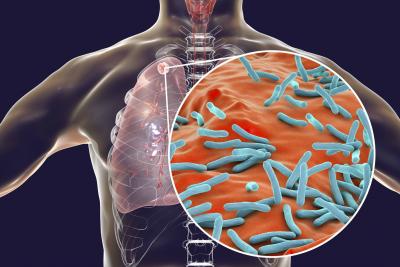

कोरोनातून बऱ्या झालेल्यांसमोर आता क्षयरोगामुळे अडचणी वाढल्या आहेत. कोरोनाच्या दुसऱ्या लाटेत लागण झालेल्या अनेकांना आता क्षयरोगाचा सामना करावा लागत आहे.

मध्य प्रदेशातील क्षयरोगींची संख्या अचानक वाढली आहे. भोपाळच्या हमीदिया रुग्णालयाच्या औषध विभागाचे प्रमुख डॉ. लोकेंद्र दवे यांनी दिलेल्या माहितीनुसार, कोरोनातून नुकत्याच बऱ्या झालेल्यांमध्ये क्षयरोगाची लक्षण दिसून आली आहेत.

हमीदिया रुग्णालयात प्रत्येक दिवसाला क्षयरोगाचे जवळपास १ डझन रुग्ण दाखल होत आहेत. भोपाळमधील सरकारी टीबी रुग्णालयात गेल्या १५ दिवसांत अनेक जण दाखल झाले आहेत. त्यापैकी बहुतांश जण कोरोना पॉझिटिव्ह होते.

कोरोनामुक्त झालेल्या अनेकांना आता क्षयरोगाची लागण होत असल्याचं विभावर उपचार करत असलेल्या डॉ. आकाश मंगोले यांनी सांगितलं. क्षयरोगाची लागण झालेले अनेकजण हे कोरोनावर मात केलेले आहेत. त्यांच्या थुंकीची चाचणी केल्यानंतर त्यांना टीबी झाल्याचं समोर आलं आहे.